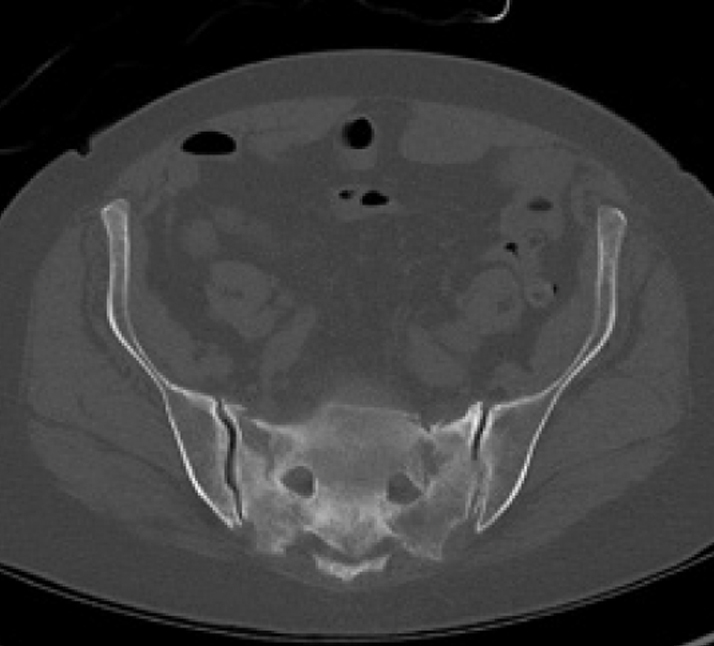

Diagnosis:

• Chronic Sacral U-type fracture with kyphotic deformity

• Anterior ring disruption

• Osteopenia

Surgical treatment:

• Bilateral sacral fracture fixation with iFuse TORQ®